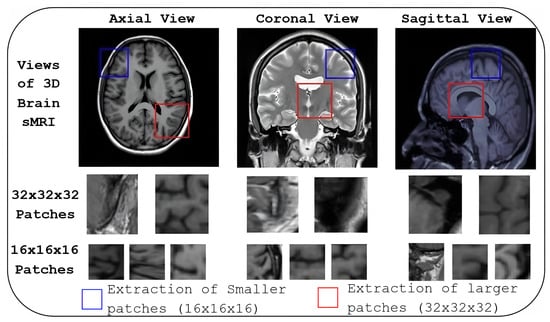

4.2.4. Dynamic 3D Patch Extraction

The CNN structure is designed to extract non-overlapping 3D patches from a brain MRI based on normalised z-scores. It dynamically adjusts the patch size according to the significance of the z-score. A normalised z-score map, representing voxel-wise z-scores for the entire 3D brain MRI, is provided as input to the designed CNN. For voxels where the z-score is greater than 1, the network extracts a larger patch of size 32 × 32 × 32, as these regions indicate higher discriminative significance. In contrast, for voxels where the z-score is less than or equal to 1, a minor patch of size 16 × 16 × 16 is extracted, as these regions are considered less discriminative.

A custom layer is implemented within the CNN to achieve this dynamic patch extraction. This layer scans the z-score map and determines the appropriate patch size for each voxel. If Z(V) > 1, a 32 × 32 × 32 patch centered at voxel V is extracted, and if Z(V) < 1, a 16 × 16 × 16 patch is extracted. The patch extraction process is non-overlapping, meaning no two patches share the same voxels. This is ensured by setting the extraction stride equal to the patch size (32 or 16), ensuring that patches are spaced apart based on their respective sizes.

This adaptive method is shown in Algorithm 1. It allows efficient 3D brain MRI data processing, focusing computational resources on regions with higher z-scores (potentially indicating abnormalities) while minimising attention to less significant regions. Importantly, by extracting patches from both hemispheres, the method enables implicit comparison across anatomically corresponding areas, allowing downstream tasks to detect asymmetrical structural changes. The network’s final output is a set of non-overlapping 3D patches, varying in size based on the z-score, which can then be used for further analysis in medical image processing including the identification of symmetry-related atrophy patterns.

6.4. Informative Patch Locations

The last two rows of Figure 6 show the informative locations of patches in sMRI identified by AMPEN. The informative patch sites in 3D Brain MRI scans are visualised in axial, coronal, and sagittal views, with patches of varying sizes, demonstrating a strategic approach to capturing relevant brain structures. The results highlight that larger patch sizes (32 × 32 × 32) are extracted from the more informative locations, and smaller patches (16 × 16 × 16) are extracted in other brain areas, ensuring a more detailed local representation while maintaining computational efficiency. These patches are identified based on the z-score, which combines both VBM and GE, and they align with regions of interest such as the hippocampus, amygdala, and thalamus—areas consistently highlighted in previous studies [22,23,25] as crucial in AD research due to their involvement in neurodegeneration. Additionally, there is a considerable association between the two tasks concerning the course of AD, as seen by the high similarity of the likely problematic regions for AD and MCI categorisation.